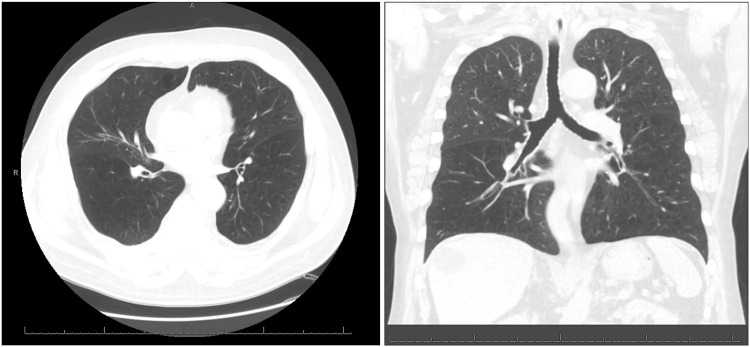

随着越来越多的州和国家将大麻用于医疗和娱乐用途合法化,吸食大麻在美国和世界上变得越来越普遍。大麻烟雾中的许多致癌物与烟草烟雾中的致癌物相似,但在文献中很难找到大麻吸烟与慢性阻塞性肺病(COPD)之间的因果关系。我们报告一位患者,其肺气肿的主要危险因素是每日吸食大麻超过35年,没有个人吸烟史,也没有其他明显的危险因素。目前的研究表明,慢性大麻吸烟与各种肺部疾患、1秒用力呼气量(FEV1)与用力肺活量(FVC)之比有关,但与慢性支气管炎不一致。有了这个病例,我们增加了目前的文献,表明长期大量使用大麻和慢性阻塞性肺病之间可能存在关系。

Marijuana smoking has become increasingly common in the United States and the world as more states and countries have legalized it for medical and recreational use. There are a number of carcinogens in marijuana smoke similar to those in tobacco smoke, and yet it has been difficult in the literature to find a causal relationship between marijuana smoking and chronic obstructive pulmonary disease (COPD). We present a patient whose main risk factor for emphysema is daily marijuana smoking for upwards of 35 years with no personal history of smoking tobacco, and no other obvious risk factors. Current studies have shown association with chronic marijuana smoking and various lung complaints, forced expiratory volume in 1 second (FEV1) to forced vital capacity (FVC) ratio, and inconsistently with chronic bronchitis. With this case, we add to the current body of literature that suggests a possible relationship between long-term, heavy marijuana use and COPD.